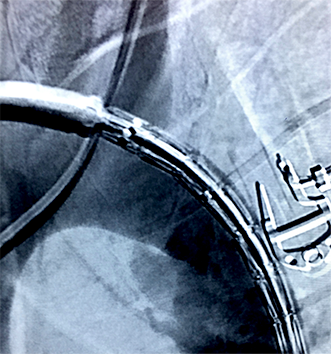

Cirurgia endovascular

- Tratamento com cateteres e guias

- Implante de stents e endopróteses

- Menor trauma cirúrgico